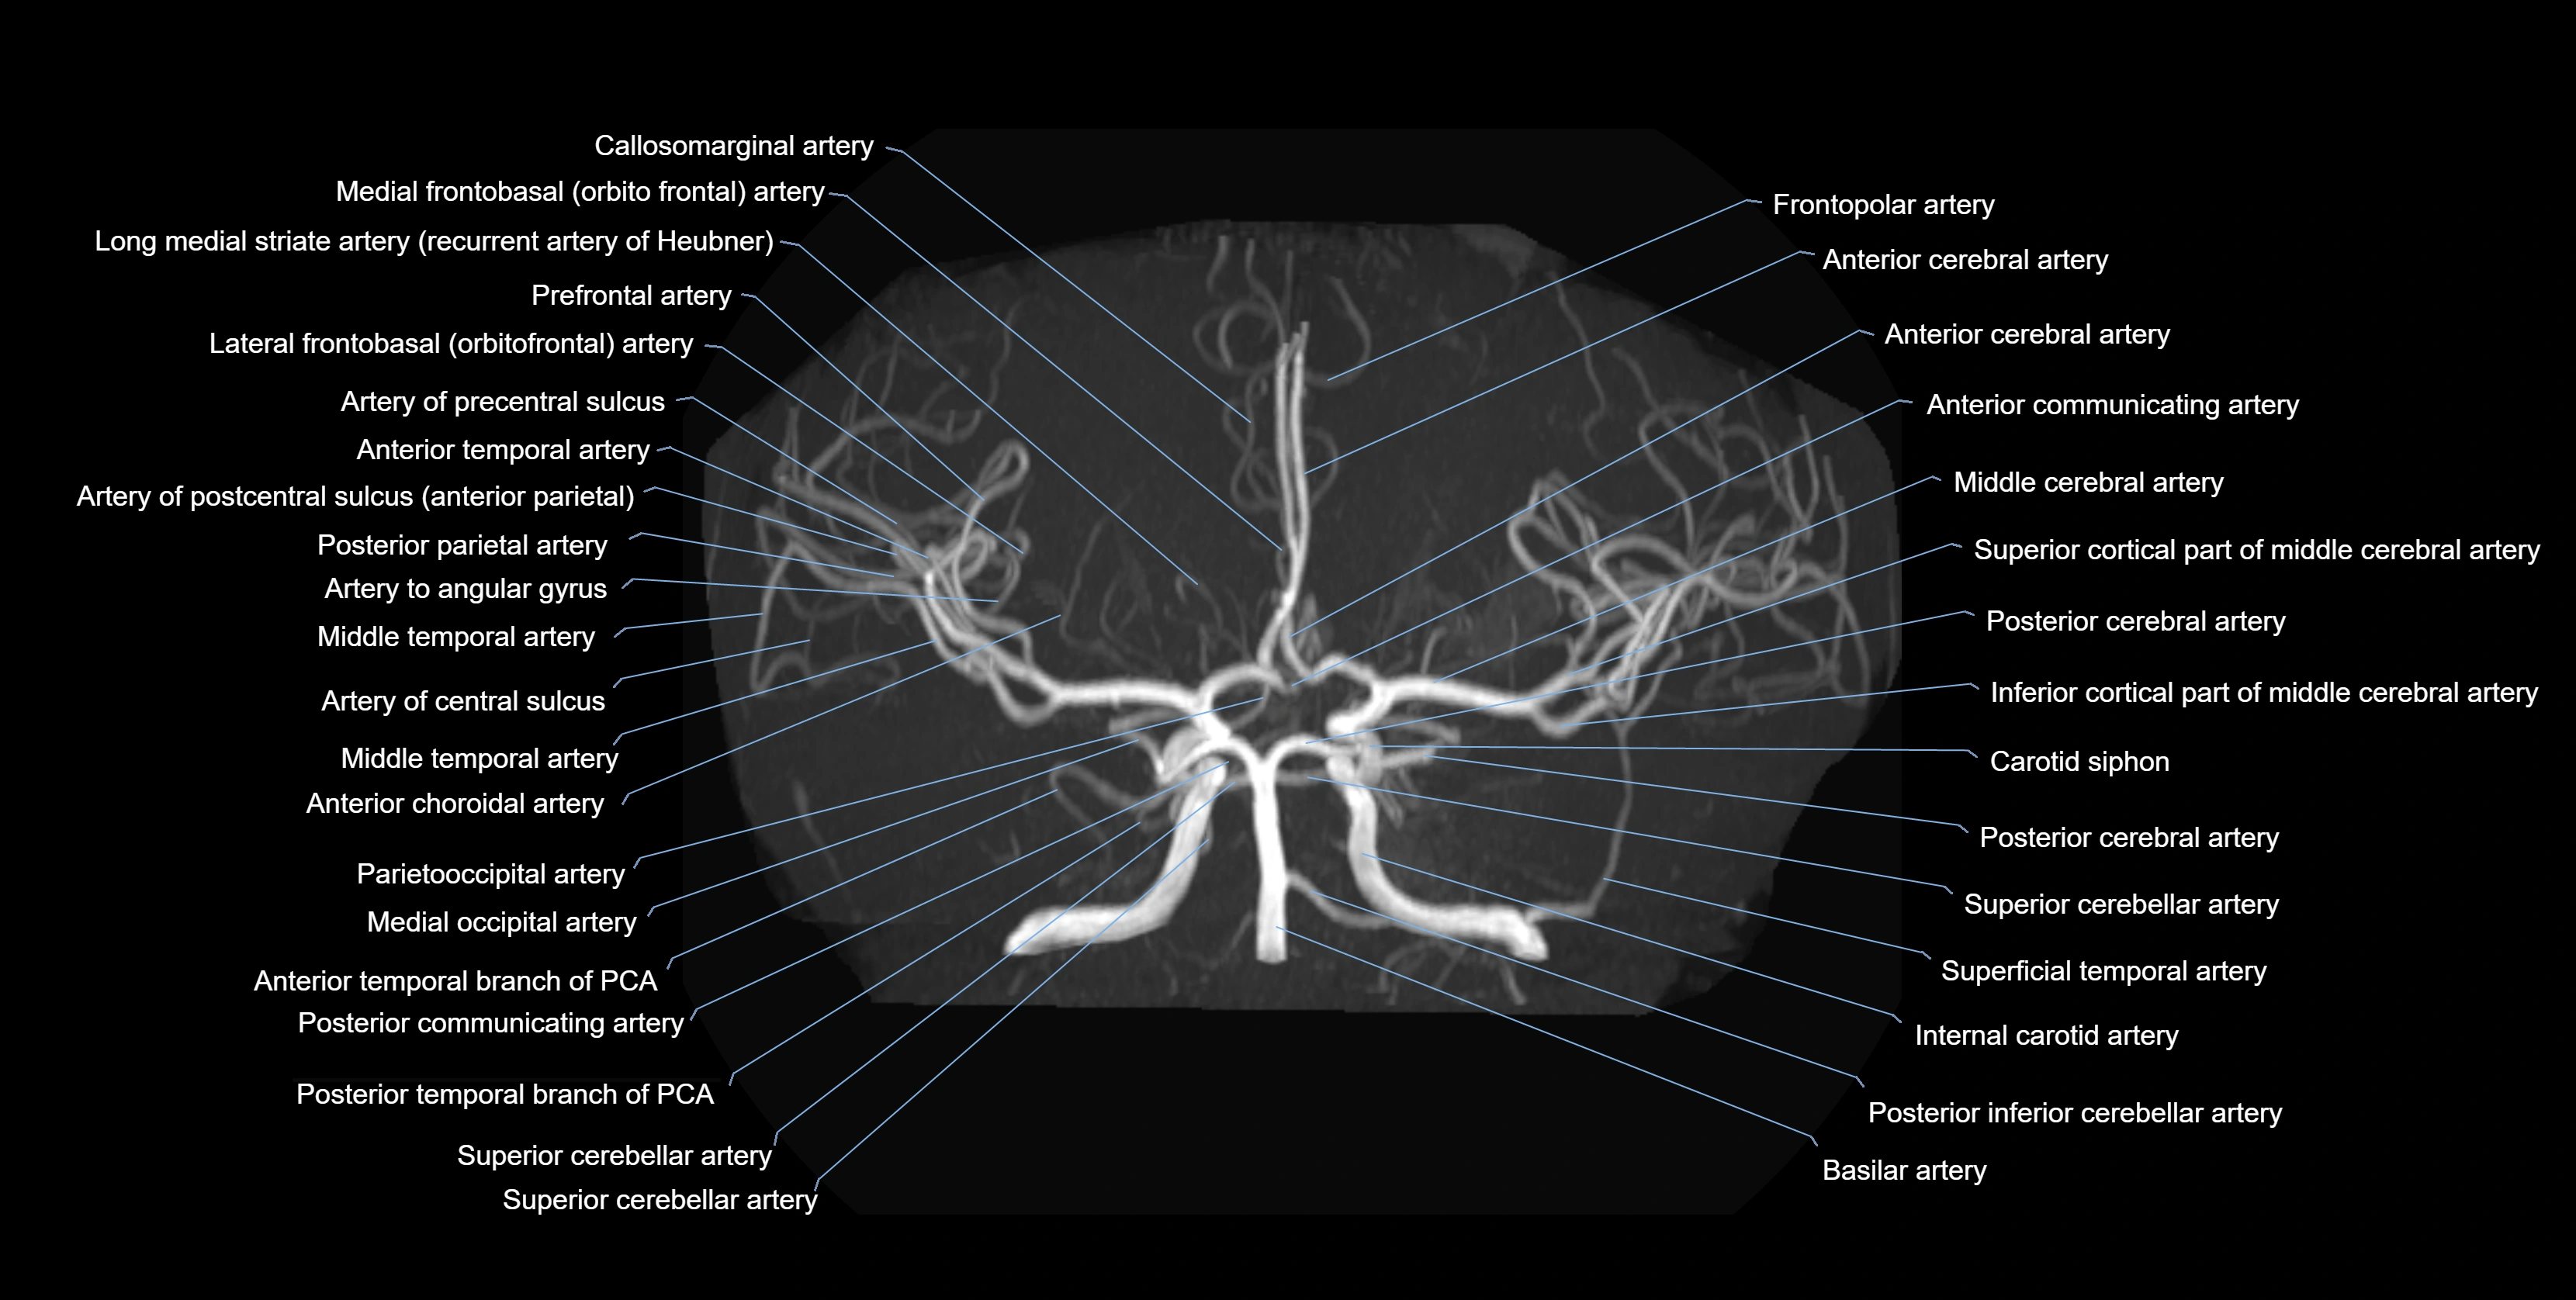

MRA (Magnetic Resonance Angiography):

• Flow-related enhancement makes the AChA appear as a bright, linear vascular signal against suppressed background

• High sensitivity for origin and proximal course; distal branches may be too small to resolve

• Detects stenosis, occlusion, aneurysm, AVM feeders

MRI images

image